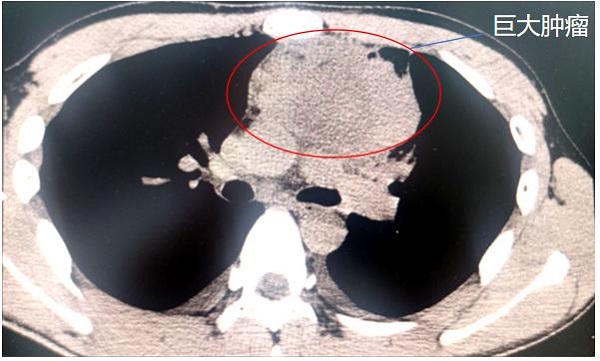

最終,在家人的陪伴下,林杰來到重醫附屬大學城醫院就診。CT檢查結果顯示,林杰的上縱隔頸胸交界處盤踞著直徑達10厘米的腫瘤,如同成年男性拳頭大小,并且緊貼心臟、主動脈弓分支及無名靜脈。

前上縱隔頸胸交界處巨大腫瘤。重醫附屬大學城醫院供圖

在重醫附屬大學城醫院胸外科辦公室,胸外科、影像科、麻醉科等專家對患者胸部CT及三維重建圖像展開激烈討論?!澳[瘤已包繞左無名靜脈”“前縱隔狹小空間操作風險極高”……種種跡象表明要順利完成這場手術并非易事,但看著患者年輕的面龐,治療團隊達成共識:必須挑戰手術禁區!